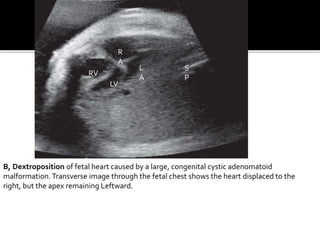

B, Dextroposition of fetal heart caused by a large, congenital cystic adenomatoid

malformation.Transverse image through the fetal chest shows the heart displaced to the

right, but the apex remaining Leftward.

B, Dextroposition offetal heart caused by a large, congenital cystic adenomatoid malformation.Transverse image through the fetal chest shows the heart displaced to the right, but the apex remaining Leftward. S P R A RV LV L A